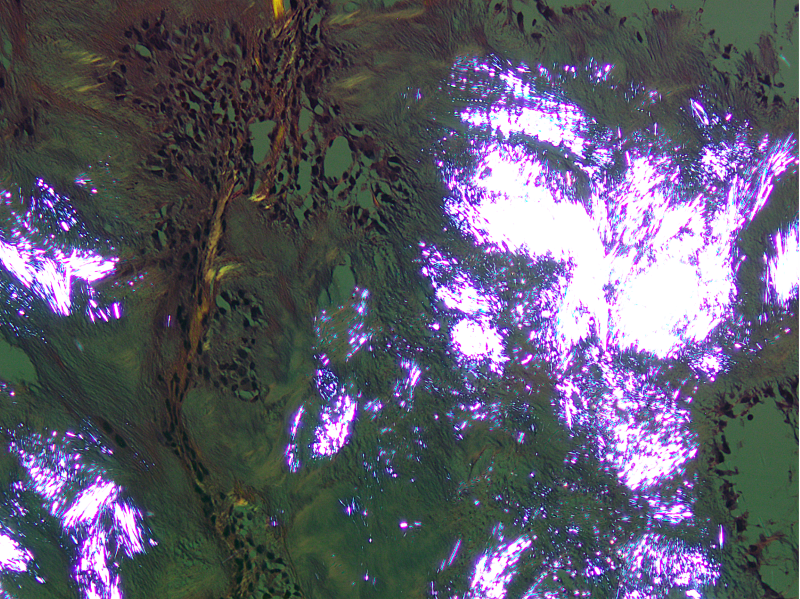

Microscopic (histologic) description

- Gout tophus:

- Nodular aggregates / granuloma-like appearance consisting of acellular, amorphous, pale eosinophilic material surrounded by palisading arrangement of histiocytes and multinucleated giant cells (Dermatol Online J 2015;21:13030)

- Feathery appearance in some deposits due to empty needle shaped spaces (Skeletal Radiol 2020;49:1325)

- Presence of monosodium urate crystals (MSU) is diagnostic

- Needle-like crystals that measure 5 - 25 micrometers in length

- Brightly anisotropic under polarized light

- Negative birefringence when examined with an interference plate in the light path (Otol Neurotol 2009;30:127)

- Crystals appear yellowish when aligned parallel to the plate axis

- Bluish appearance when alignment is across the direction of polarization

Microscopic (histologic) images